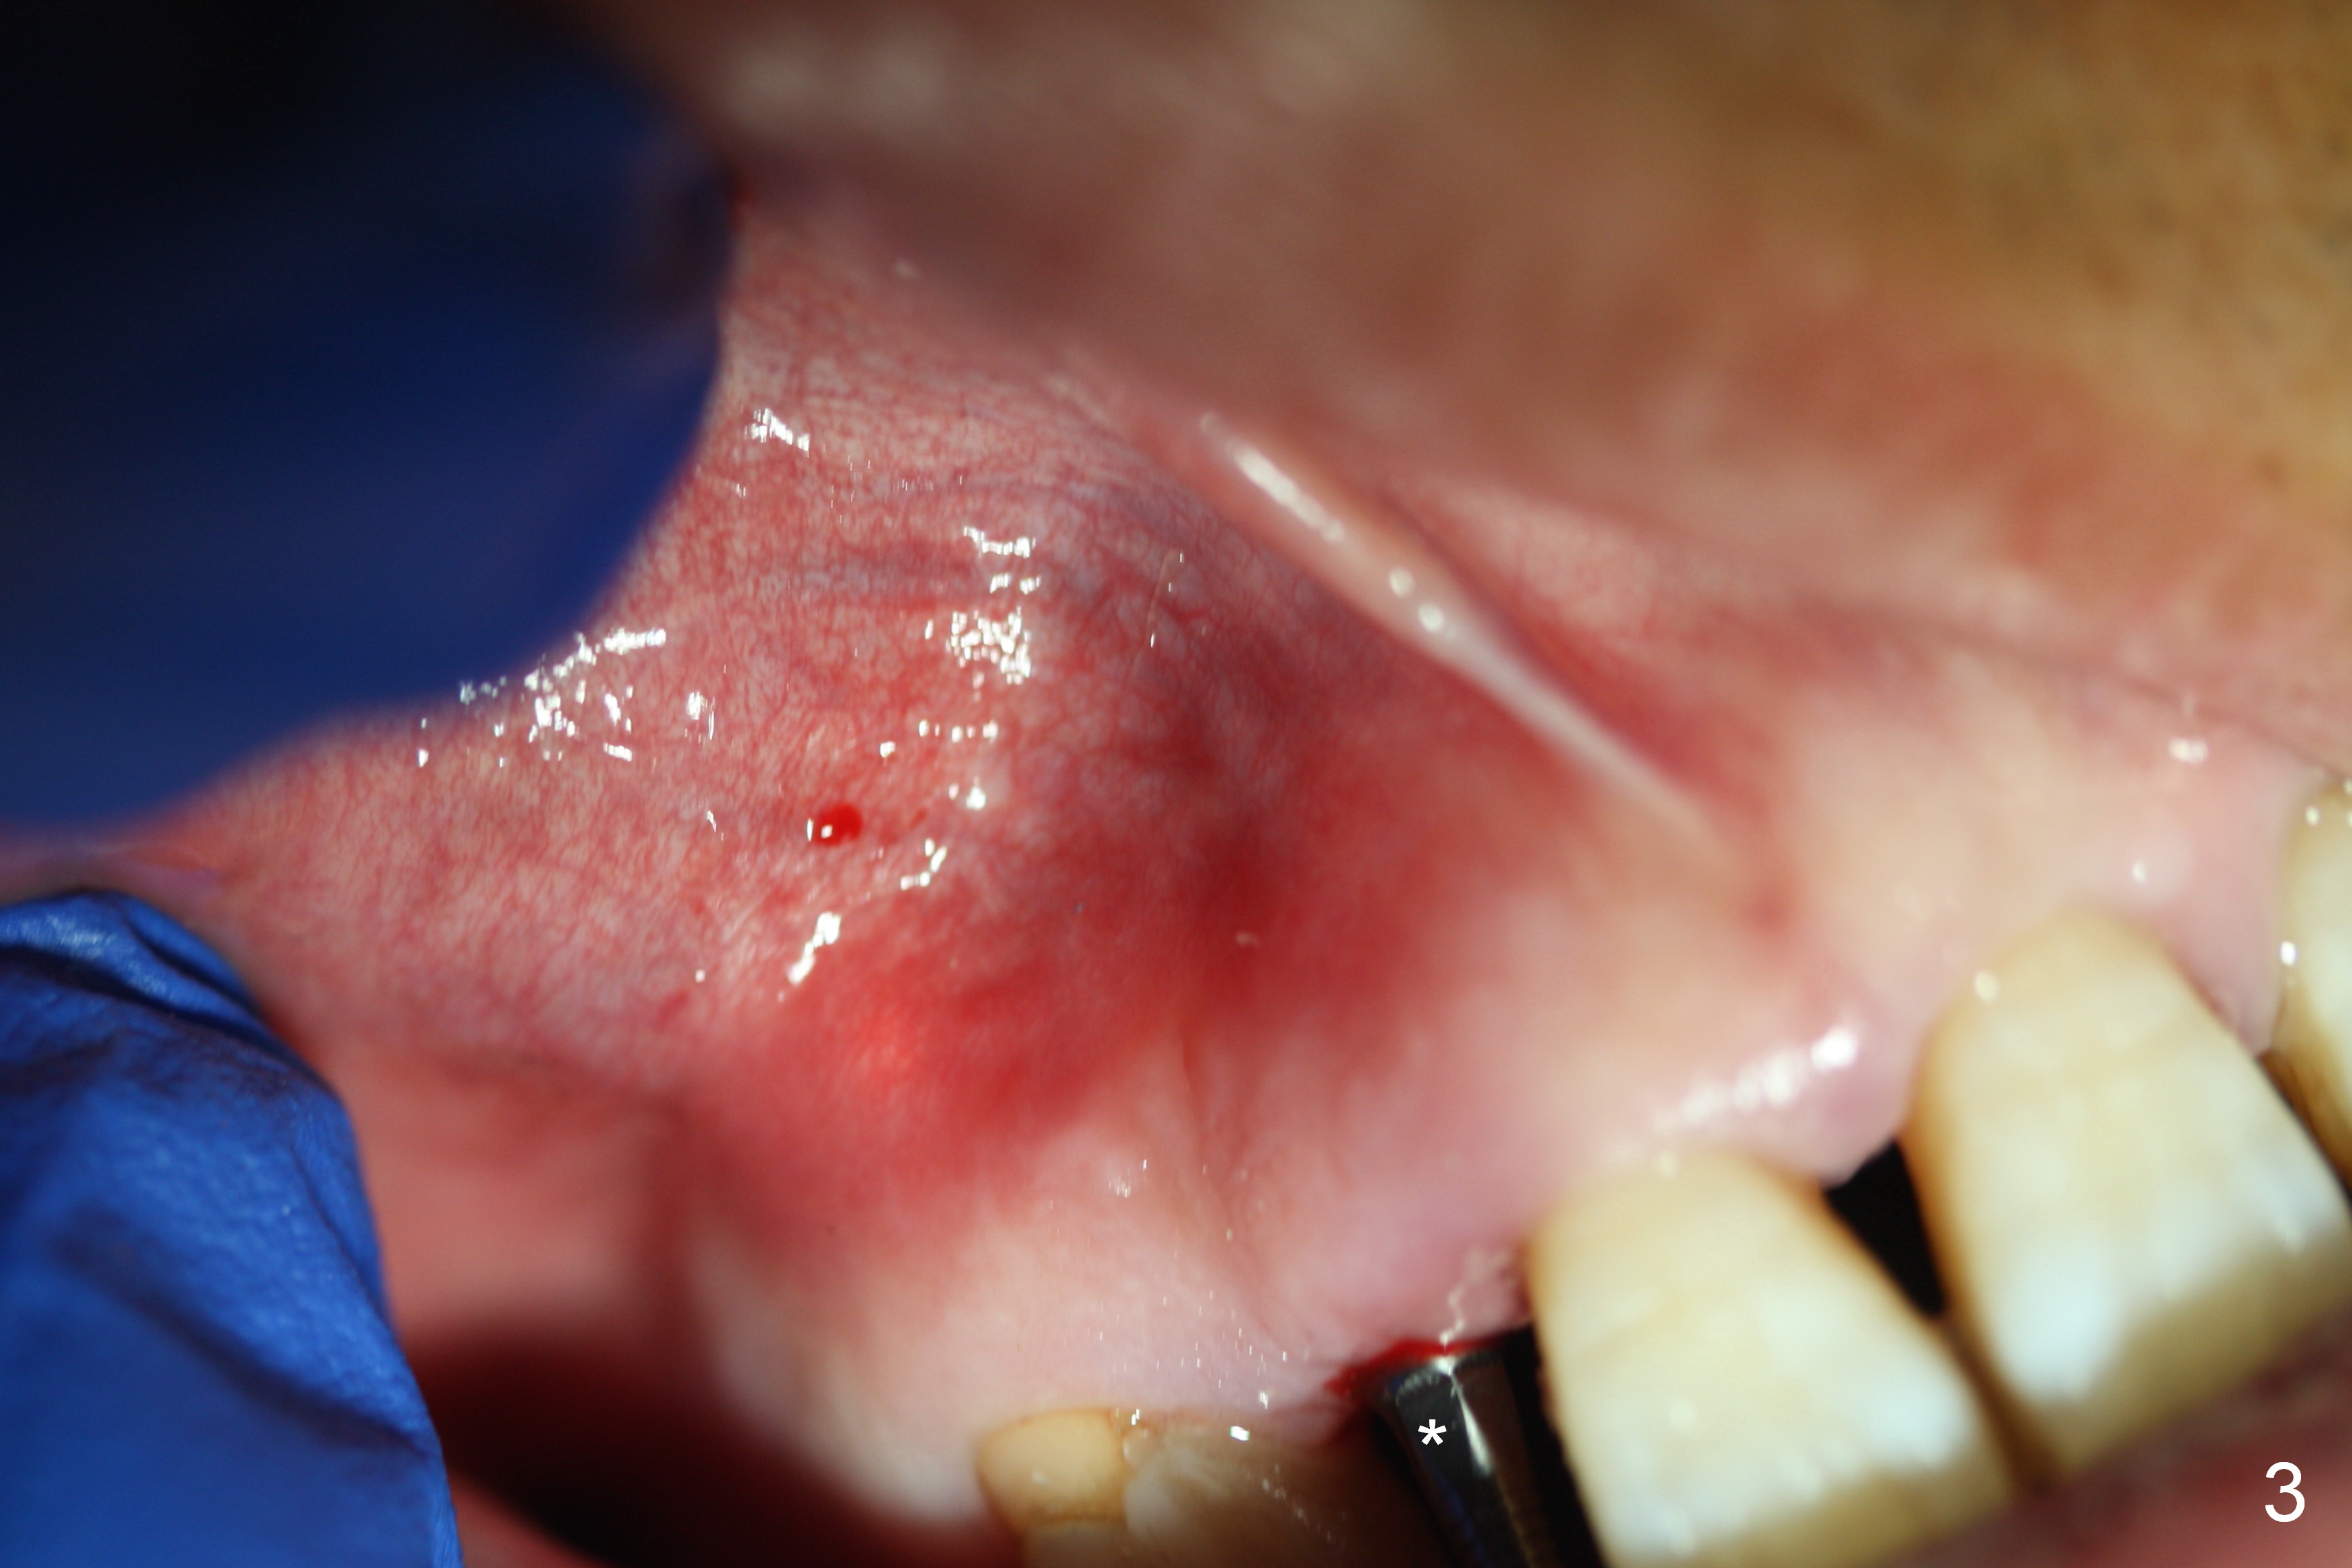

Apical Buccal Plate Perforation

Preop exam shows the apparent wide ridge at #7 (Fig.1). What is ignored preop is the concavity in the apical buccal region (Fig.2 *). When a 3x16(4) mm 1-piece implant is being placed (Fig.3 *, flapless), the apical buccal plate vibration is felt. The biggest mistake is that initial osteotomy is ~ 6 mm shy of the implant length, partially because of 6 mm gingival height. Since the tooth #6 is symptomatic after RCT with paste overfill (Fig.4 >), apicoectomy is contemplated at #6 with exploration of the buccal plate at #7 (Fig.5). Since the implant appears to be long enough, implant apical resection is performed (Fig.6). Since there is coronal thread exposure due to previous periodontitis (Fig.7 <), bone graft is placed in these 3 defective areas after decortication.

Extending the initial osteotomy to the full length of the implant is critical. If perforation is detected early, the trajectory can be changed. Incision should be made if there is no CBCT study. The incision heals 1 and 4 weeks postop (Fig.8,9). The patient returns for final restoration 6 months postop. Apical defects appear to have healed at #6 and 7 (Fig.10,11). Fig.12 is taken 11 months postop and 5 months post cementation. The patient has an accident 9 months post cementation. In fact the implant is alright, while the tooth #6 fractures and #8 subluxates.